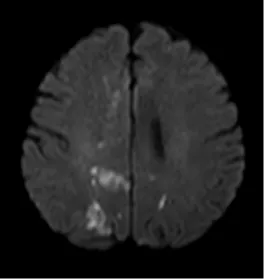

近日,一名58岁的男性患者因“双膝关节麻木”入住我院脑病科一病区,初诊怀疑腰椎问题,次日出现感觉异常,经磁共振(MRI)检查,结果显示他患有双侧额顶叶多发新鲜脑梗死,经抗血小板、强化降脂等常规治疗后好转,但短短3天后,患者症状便再次发作,复查磁共振显示,患者又出现多处新发脑梗死,且症状较上次更明显。面对常规治疗无效的困境,脑病科一病区医疗团队迅速调整思路,通过血栓基因检测,发现患者对他汀类药物反应特殊,随即调整降脂方案。更关键的是,患者双侧大脑半球的多发脑梗死发生在不同的时间段,不同部位,这使得病因的进一步明确成为治疗的关键。

患者再次就诊,出现了新的脑梗死病灶